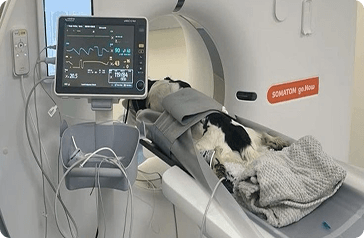

CT vizsgálatok

A CT vizsgálat egy rendkívül gyors és pontos diagnosztikai eljárás, melynek segítségével a test bármely része feltérképezhető.